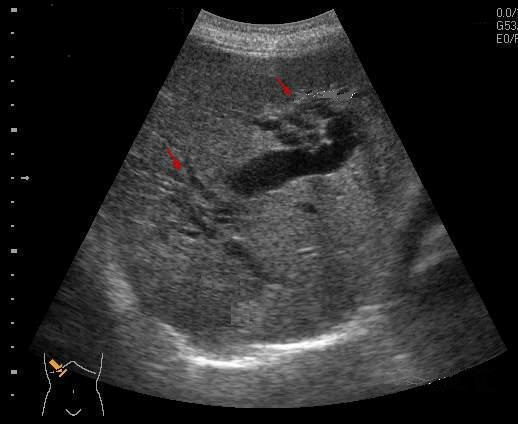

Angiocholite aigue

bacterienne . Image de dilatation

hypoechoriche des voies biliaires

intrahepatiques avec epaissisement legere de

sa paroi ( fleche rouge ) . Image

echographique per cutanee , coupe

hypochondre droit a travers foie droit |

Cholangite infectueuise aigue de

voie biliaire intrahepatique . Image de

dilate tres marque des voie biliaire du foie

droit avec distendue du canal hepatique

commun . Epaississement legere de la

paroi intrahepatique |